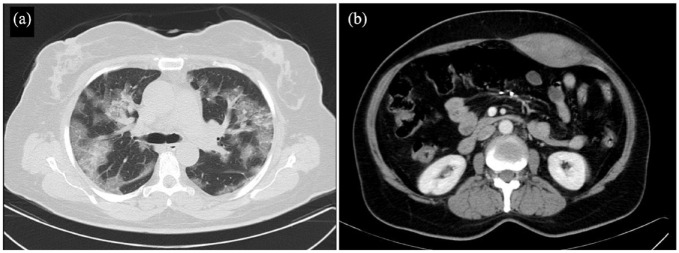

The COVID-19 pandemic has had an enormous impact on the healthcare systems. Along with its common complications, novel complications such as Rectus Sheath Hematoma (RSH) have been reported. We present 2 cases of RSH. (A) A 63-year-old woman with a known case of COVID-19 with severe cough presented sudden tachycardia and hypogastric pain; on physical examination, a huge lower abdominal tender mass was noticed. All the differential diagnoses were ruled out. (B) A 57-year-old woman with COVID-19 started complaining of tachycardia, pain, and a mass in the lower abdomen. On the physical examination, a lower abdominal tender mass was noticed. Both of the patients underwent an abdomen CT scan which confirmed a huge RSH. Conservative treatment and cessation of anticoagulant medications were continued. Both of them recovered and no evidence of further expansion was seen after 4 weeks of follow-up.